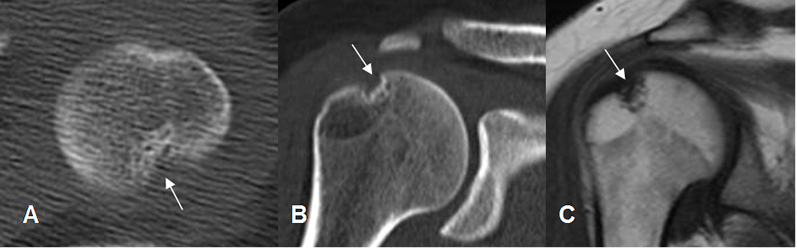

Fig 97. Pinzamiento postero superior.

A: TAC axial: Lesión osteocondral en la parte posterior de la cabeza humeral.

B: TAC reconstrucción coronal y C: RM sagital en T1. Lesión osteocondral en el borde posterosuperior de la cabeza humeral, por pinzamiento.